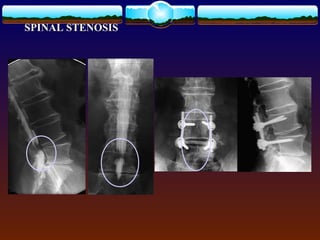

Lumbar Spinal Stenosis Normal canal  “Narrowing of osteoligamentous vertebral canal and/or the intervertebral foramina causing compression of the thecal sac and/or the caudal nerve roots”  Classification  ----congenital  -----aquired

Evaluation  AP &Lat radiographs 20-16  Flex/ext films to reval stability  CT 16-11  MRI  Lumbar myelography + CT  Evaluation of extent of neural element compression

• 55.

• 56.

• 57.